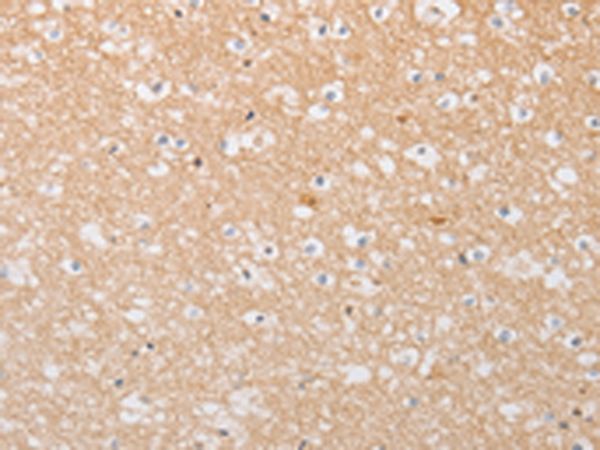

分类: 科研抗体货号: P08004别名: mATG9; APG9L1; MGD3208应用: WB,IHC反应种属: Human, Rat